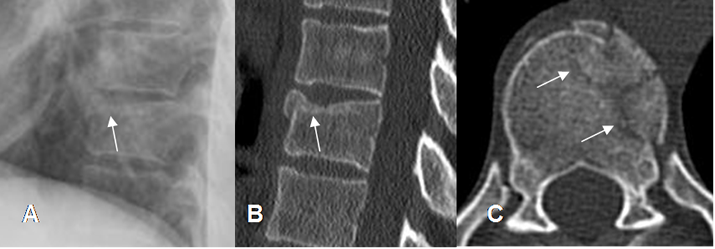

Fig 159. Fractura estable.

A: Rx lateral, B: TAC reconstrucción sagital y C: TAC axial. Fractura en la parte anterosuperior del cuerpo vertebral, con compromiso solo de la columna anterior.